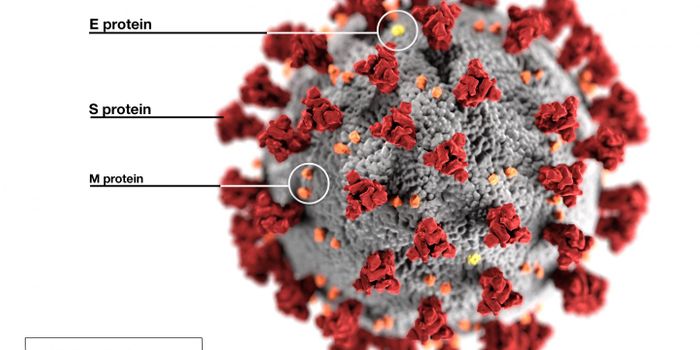

MAR 17, 2020ImmunologyStructurally, SARS-CoV-2 (the virus that causes COVID-19) are spherical shells consisting of a lipid membrane, with a co ...